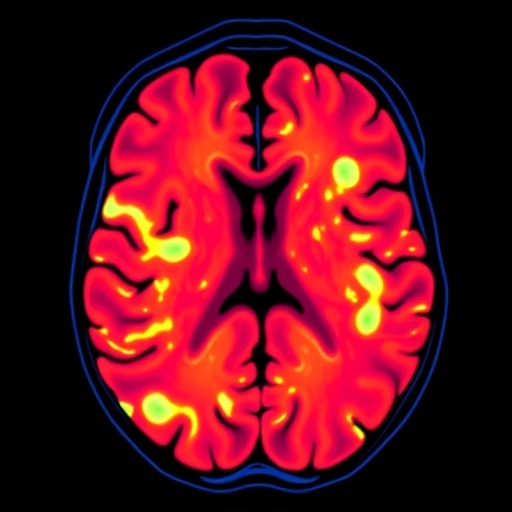

Traditional radiomics involves extracting quantitative features from medical images that characterize tumor heterogeneity, shape, and texture. However, these features alone can capture only a fraction of the full complexity inherent in tumor biology. To transcend this limitation, the researchers incorporated three-dimensional deep learning features derived from both the entire DCE-MRI volume and focused tumor regions. This fusion enabled the model to harness subtle imaging cues and spatial relationships invisible to conventional methods.

Critically, the investigation focused on two distinct temporal phases of the DCE-MRI scans—the early enhancement phase and the peak enhancement phase. These intervals reflect different physiological and vascular properties of the tumor microenvironment, providing complementary insights into tumor perfusion and permeability. By merging features from these phases, the team hypothesized that predictive accuracy could be significantly bolstered.